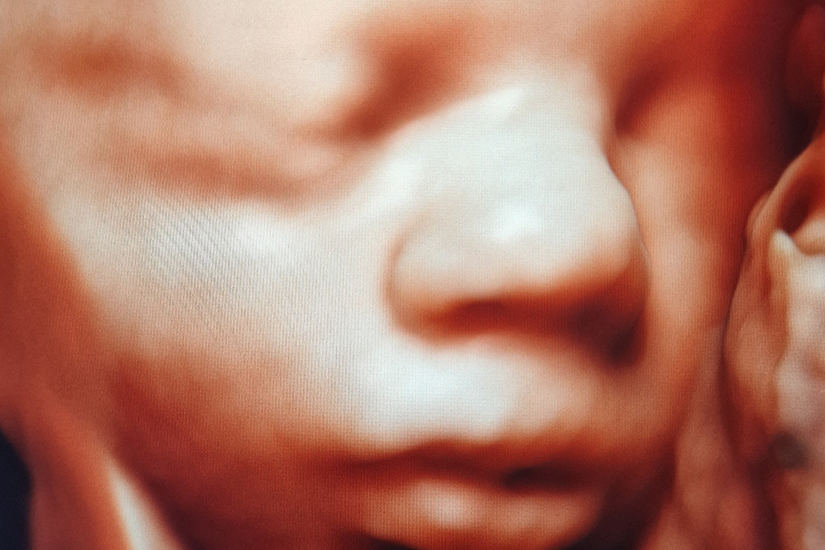

Acum fatul poate fi evaluat inca din primele etape de dezvoltare cu imagini 2D, 3D si 4D care descriu cele mai mici detalii cu o rezolutie inalta si permit masuratori mai exacte. Utilizarea ecografului Voluson Expert 22 ajuta la imbunatatirea ratelor de detectare a anomaliilor cromozomiale si morfologice ale fatului, pentru diagnosticarea posibilelor patologii in timpul sarcinii, oferind raspunsuri precoce pentru o mai buna luare a deciziilor.

Este un ecograf perfect pentru femeile insarcinate si pentru tatii care, dupa ce au aflat ca totul este bine, isi doresc experienta unica si emotionanta a primei fotografii a copilului lor - aceea de a vedea fata bebelusului lor intr-o imagine 3D/4D de cea mai buna calitate.